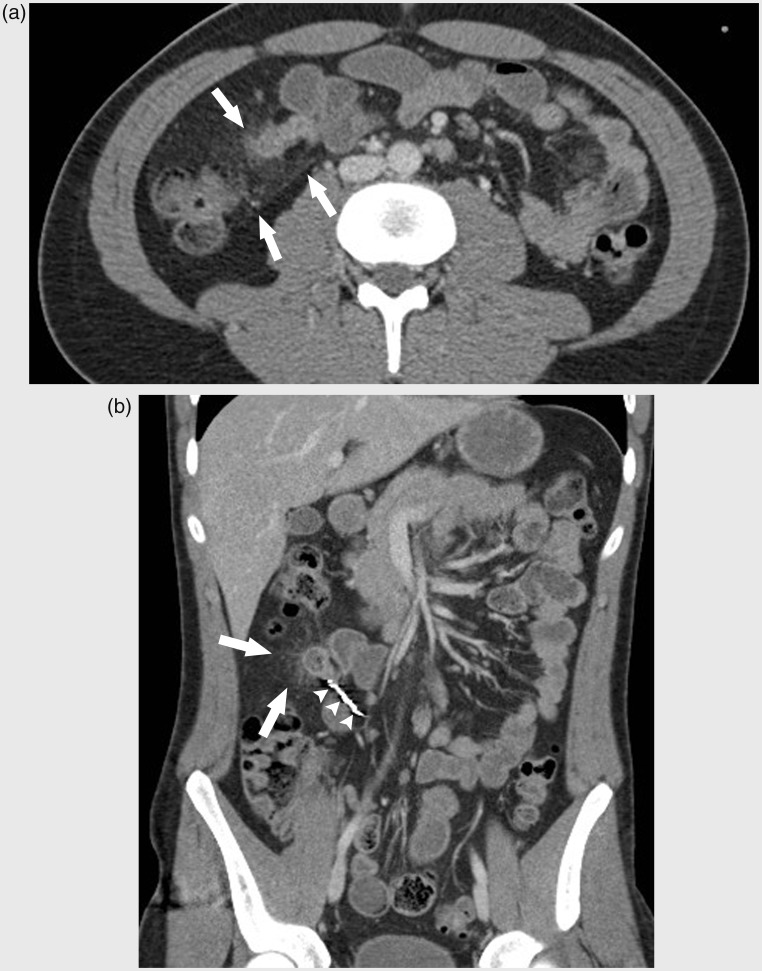

A 23-year-old man presented with hypovolemic shock due to a lower gastrointestinal bleeding. Radiological and endoscopic investigation did not reveal the bleeding site. Emergency visceral angiography showed contrast extravasation at a right-sided branch of the superior mesenteric artery (SMA). Embolization of the bleeding point was performed, resulting in bleeding cessation. One week later, the patient presented with a new episode of moderate anal blood loss associated with diffuse abdominal pain. Computed tomography (CT) revealed an ischemic small bowel diverticulum that was treated by a laparoscopically-assisted segmental small bowel resection. Intraoperative and pathologic analysis confirmed a post-embolization ischemic diverticulitis of Meckel.